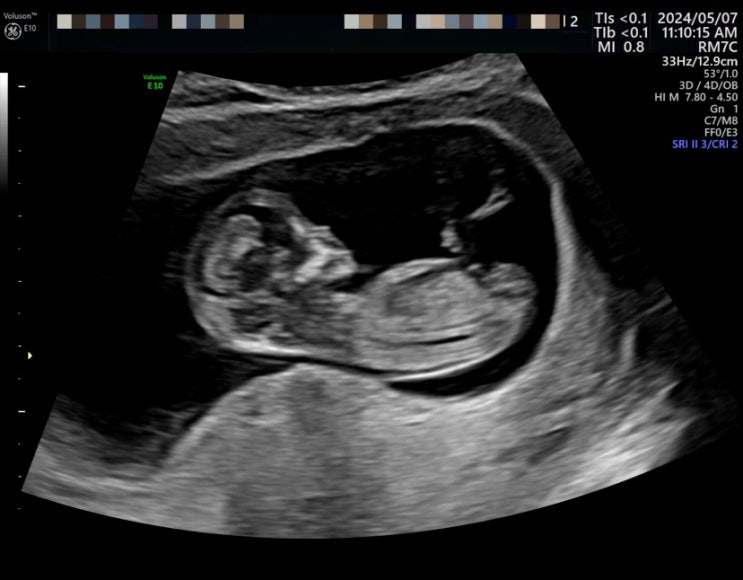

[임신12주]목투병대검사와 산전선별검사

드디어 그 날이 왔다. 아이의 기형여부를 1차적으로 판단할 수 있는 목투명대 검사일. 둘째인 쓰담이는 목...

[임신8주] 귀욤이는 잘 자라나, 아내는 입덧 고생 중

운이 좋게 시험관 1차례 시도로 자리를 잘 잡아준 귀욤이. (귀욤이는 토닥이가 지어준 이름) 8주차에 2.4cm...